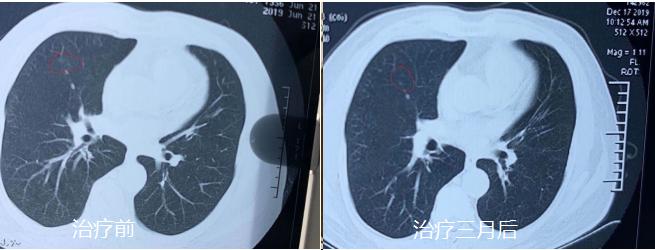

经3个月的中医调方治疗,患者身体状况不断改善。2019年12月17日患者上当地医院复查,提示结节明显缩小。当时为其做检查的医生通过电脑测得患者的结节已缩小至0.1cm。患者感慨幸好当时坚持不手术,沉重的心情也豁然开朗了,对接下来的治疗也更有信心。目前该患者仍在服用中药继续巩固治疗当中。

治疗前和治疗后对比

治疗三个月复查,结节明显缩小